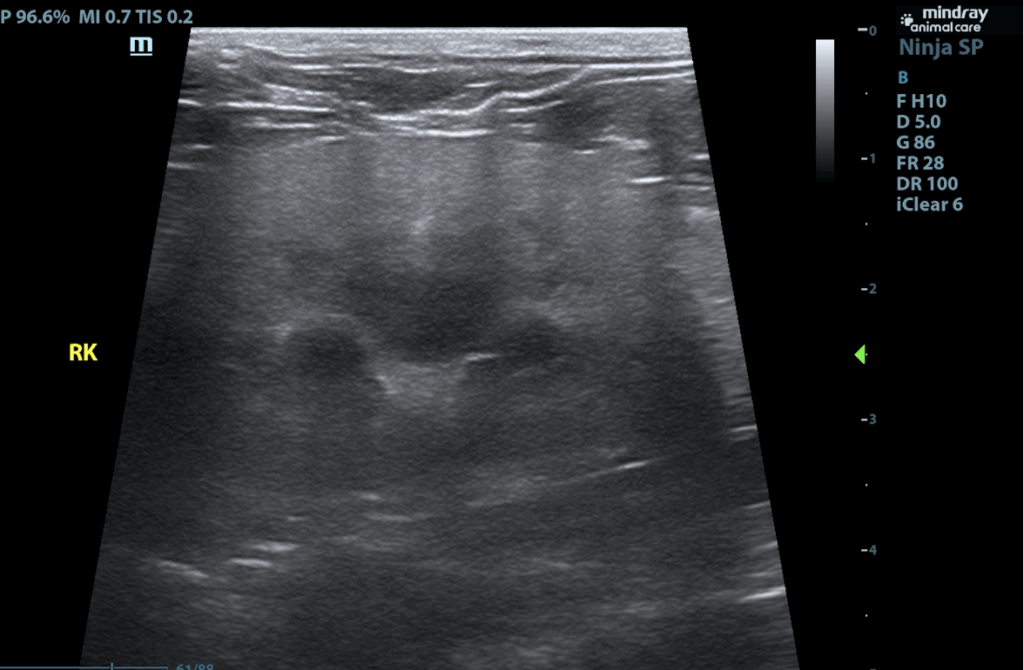

The urinary bladder is adequately distended with anechoic contents. No masses, inflammatory changes, echogenic sediment or cystoliths are observed. The urinary bladder, trigone and visible pelvic urethra are normal in thickness with a smooth mucosal surface. Kidneys are normal in size and contour. A relatively uniform hyperechogenicity is observed with mildly decreased corticomedullary distinction. There is no pyelectasia noted and no mineral is observed. No overt masses/nodules are observed. The left kidney measures 4.19 cm. The right kidney measures 4.33 cm.

The right adrenal gland is normal in size (0.38 cm at cranial pole and 0.31 cm at caudal pole), shape and overall architecture, echogenicity and echotexture. Visible surrounding vasculature appears normal. The left adrenal gland is enlarged, measuring 1.8 cm long x 1.2 cm thick at the caudal pole, with mild heterogeneous parenchymal changes and an overall egg-shaped hypoechoic appearance, with swollen capsular expansion noted but no evidence of capsular escape or vascular invasion.